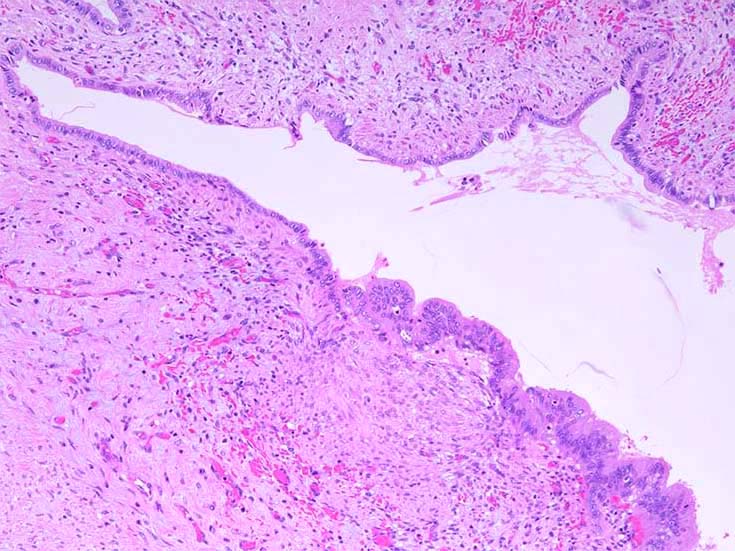

膵上皮内腫瘍性病変 pancreatic intraductal neoplasm(PanIN)*16

Low-grade PanINとhigh-grade PanINの分類

low-grade PanIN

PanINの図譜はJohns Hopkins The Sol Goldman Pancreatic Cancer Research CenterのHome page*19から引用.

1. PanIN-1; PanIN発生の初期段階. 組織学的に, 核異型を伴わない, 核の極性が保たれている.

• telomereの短縮

• KRAS変異

• p16/CDKN2A変異

• Mucin(MUC)発現